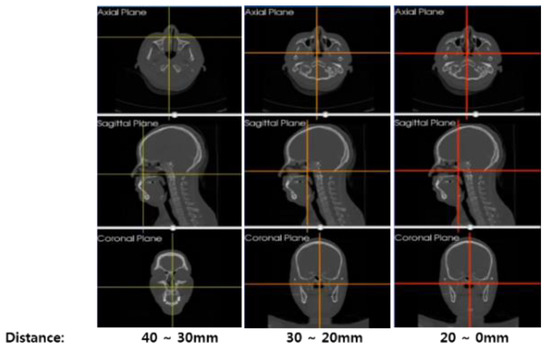

3.1. Proposed Surgical Navigation System

3.2. Registration for Construction of Navigation System